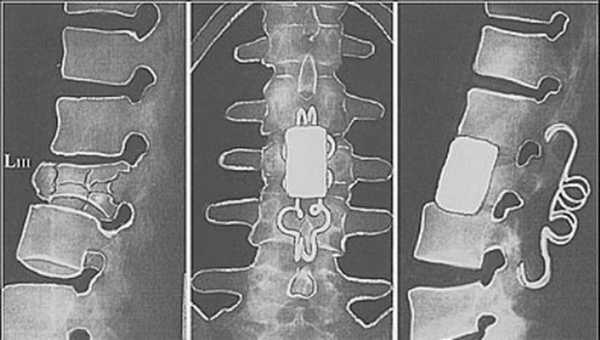

(Слева) КТ, аксиальный срез: перелом С5 позвонка с сагиттально ориентированной плоскостью перелома тела позвонка, характерной для взрывных переломов, переломом корня и пластинки дуги справа.

(Справа) На сагиттальном STIR МР-И отмечается отек костного мозга на фоне компрессионных переломов тел позвонков. Также видны признаки контузии спинного мозга, задних связок и паравертебральных мышц. (Слева) КТ, сагиттальный срез (костный режим): оскольчатый взрывной перелом С5 с вертикально ориентированной плоскостью перелома и снижением высоты позвонка. Задний фрагмент тела смещен в спинномозговой канал. Кроме этого имеет место перелом заднего края и С4 по звонка.

(Справа) КТ, аксиальный срез (костный режим): оскольчатый взрывной перелом С5 позвонка с вертикально ориентированной плоскостью перелома, задним смещением и ротацией фрагмента. Перелом распространяется на правый корень и пластинку дуги. (Слева) КТ, аксиальный срез (костный режим): типичный взрывной перелом тела шейного позвонка, характеризующийся наличием сагиттального и фронтального компонентов. Также здесь имеется место перелом суставного отростка и пластинки дуги справа, что свидетельствует о наличии ротационного компонента повреждения.

(Слева) КТ, фронтальный -срез: вертикальная линия перелома тела C5 у пациента с взрывным переломом С5 позвонка. Кроме этого в области верхней части тела С6 позвонка видна линия переломав.

(Справа) На сагиттальном T2*GRE МР-И у пациента с взрывным переломом тела С5 ЕЯ отмечается распространенный отек и низкоинтенсивный очаг кровоизлияния в паренхиму шейного отдела позвоночника. Определяется умеренная дислокация заднего фрагмента тела С5 в спинномозговой канал. (Слева) КТ, сагиттальный срез: взрывной перелом С5 позвонка Я с небольшим снижением высоты его тела, а также еще один, менее тяжелый, перелом С4 и перелом задних элементов С6 позвонка.

(Справа) КТ, фронтальный -срез (костный режим): взрывные переломы С4, С5 и С6 позвонков с преимущественно сагиттальным расположением плоскости перелома тел позвонков. (Слева) На аксиальном GRE МР-И у пациента с взрывным переломом позвонка видна сагиттальная линия перелома Я и нарушение целостности правой пластинки дуги.

(Справа) КТ, аксиальный срез (костный режим): пациент с компрессионной травмой шейного отдела позвоночника виден сагиттальный перелом тела позвонка, а также переломы правой и левой пластинок дуги.